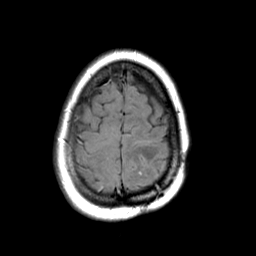

MR Study #3 -- Slice #44